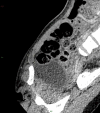

We report the case of a 32-year-old woman who presented with reducible indirect inguinal hernia and a challenging constellation of symptoms, signs and radiographic findings. Surgical approach superseded conservative management when the patient's abdomen became acute, with a rising lactate and haemodynamic instability. Specifically, the presence of a fluid collection was concerning for sinister acute pathology. Our patient was rediagnosed intraoperatively with hydrocoele of canal of Nuck. This so-called 'female hydrocoele' is an eponymous anatomical rarity in general surgery, presenting as an inguinolabial swelling with variable clinical profile. Hydrocoele of canal of Nuck takes origin from failure of transitory reproductive anlagen to regress and is thus analogous to patent processus vaginalis. Its true incidence is speculative, with just several hundred cases globally. We aim to provide insights into surgical patient management for a rare entity during the COVID-19 outbreak, from the unique perspective of a small rural hospital in Scotland.